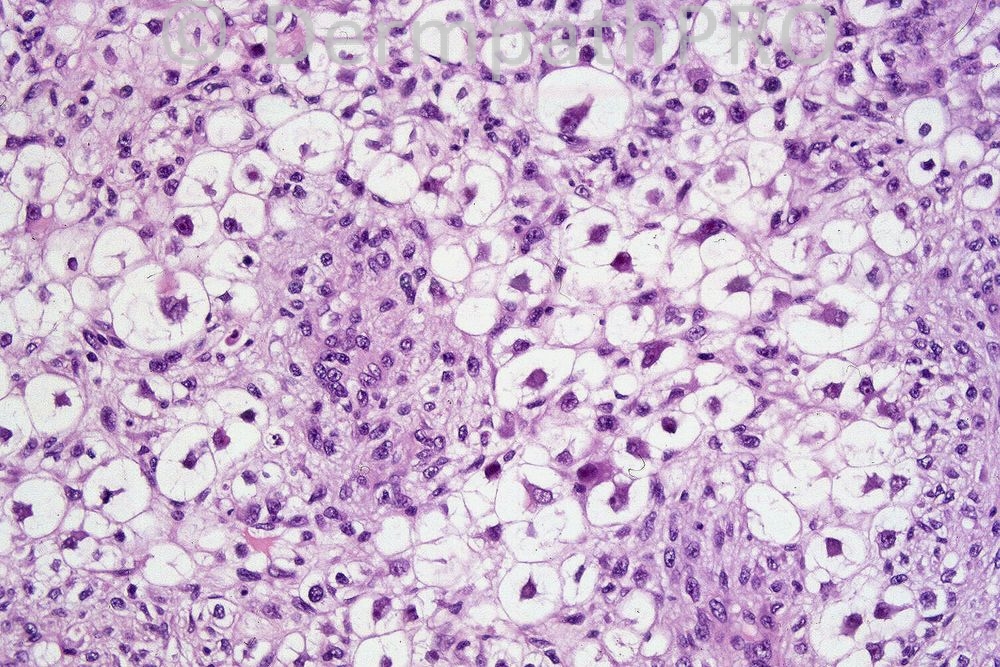

Again I have to go out for most of the day and so am posting the answer early. The tumor does show very focal sebocytes with crenated nuclei although I do agree that the majority show clear cell change. The nuclei are pleomorphic and hyperchromatic. The lesion is a poorly differentiated sebaceous carcinoma in which sebaceous differentiation is often focal and difficult to find. I like the differential diagnoses of clear cell SCC, clear cell porocarcinoma or hidradenocarcinoma. Clear cell melanoma is also an important consideration.

In this section I would rather think of tumors with clear cell changes rather than sebacous neoplasm. Some of the cells have ecenteric nuclei (signet ring cell like), the cytoplasm looks clear to finely reticulated, not foamy and bubbly like that of sebocytes. Moreover, in the right lower part of the field, I can percieve esinophilic cytoplasm around the nuclei which is then surrounded by clear spaces.. I thought of clear cell SCC (the non keratinizing variant which does not show foci of keratinization or the pleomorphic type wich may show microcysts containing acantholytic cells).The other possibility is a hidraadenocarcinoma or a porocarcinoma with clear cell change (may be else where there is evidence of ductal differentiation). Clear cell renal carcinoma is not the case as well as balloon cell melanoma.